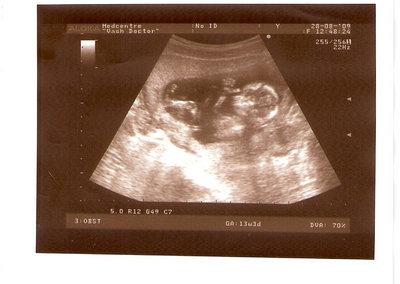

СЫН

| Вложения: |

2.jpg [ 110.14 КБ | Просмотров: 2810 ]

13 НЕД И 5 ДНЕЙ

3.jpg [ 96.81 КБ | Просмотров: 2808 ]

Nikisa писал(а): Foto prosto chudesnoe. A na kakom sroke uznali, chto sin.............. НА 13 НЕДЕЛЯХ.КАК РАЗ ВОТ В ЭТО узи, ОНО УМЕНЯ ВТОРОЕ БЫЛО. ЭТО КОНЕЧНО МАЛЕНЬКИЙ СРОК ДЛЯ ОПРЕДЕЛЕНИЯ ПОЛА. НО Я ПОПРОСИЛА ВРАЧА(ЭТО КТСТАТИВ РОССИИ БЫЛО) ХОТЯ БЫ ПРЕДПОЛОЖИТЬ. ЕЙ ВСЁ ТАКИ УДАЛОСЬ РАССМОТРЕТЬ.НУ ВООБЩЕМ ЧЕРЕЗ НЕСКОЛЬ ДНЕЙ ПОЙДУ К ВРАЧУ, УЖЕ АМЕРЕКАНСКОМУ И УЗНАЮ ТОЧНО. К ТОМУ ВРЕМЕНИ У МЕНЯ БУДЕТ СРОК 18 НЕДЕЛЬ. ХОТЕЛОСЬ БЫ ПОСМОТРЕТЬ НА ДРУГИЕ ФОТО НА ЭТОМ СРОКЕ ИЛИ БОЛЬШЕ. ТАК ЧТО ВЫКЛАДЫВАЙТЕ, ЕСЛИ НЕ ЖАЛКО!